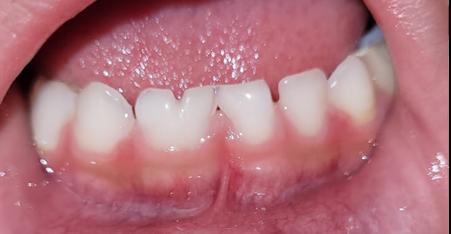

Se aplica un proceso de arbitraje en pares doble ciego de forma anónima, objetiva, consistente y con crítica constructiva. Los árbitros no tienen ningún vínculo de tipo laboral, académico o personal con los autores.

Todo manuscrito que no se adecúe a estos principios y se compruebe una mala práctica será eliminado o retractado, en función del estado en que se encuentre en el momento de detectar faltas éticas.

1. Carpio-Deheza G. Manual de instrucciones para la presentación de protocolos y monografías de diplomados, protocolos y tesis de espcialidad clínica/ quirúrgica, tesis de maestrías y doctorados en salud. Cochabamba: Universidad Mayor de San Simon, Facultad de Medicina Dr. Aurelio Melean, post grado UMSS; 2019.

2. Patrias K. Citing Medicine; The NLM Style Guide for Authors, Editors, and Publishers. [Online].: Bethesda (MD): National Library of Medicine (US); 2007 [cited 2022 marzo 29. Available from: https://www.ncbi.nlm.nih.gov/books/NBK7256/.